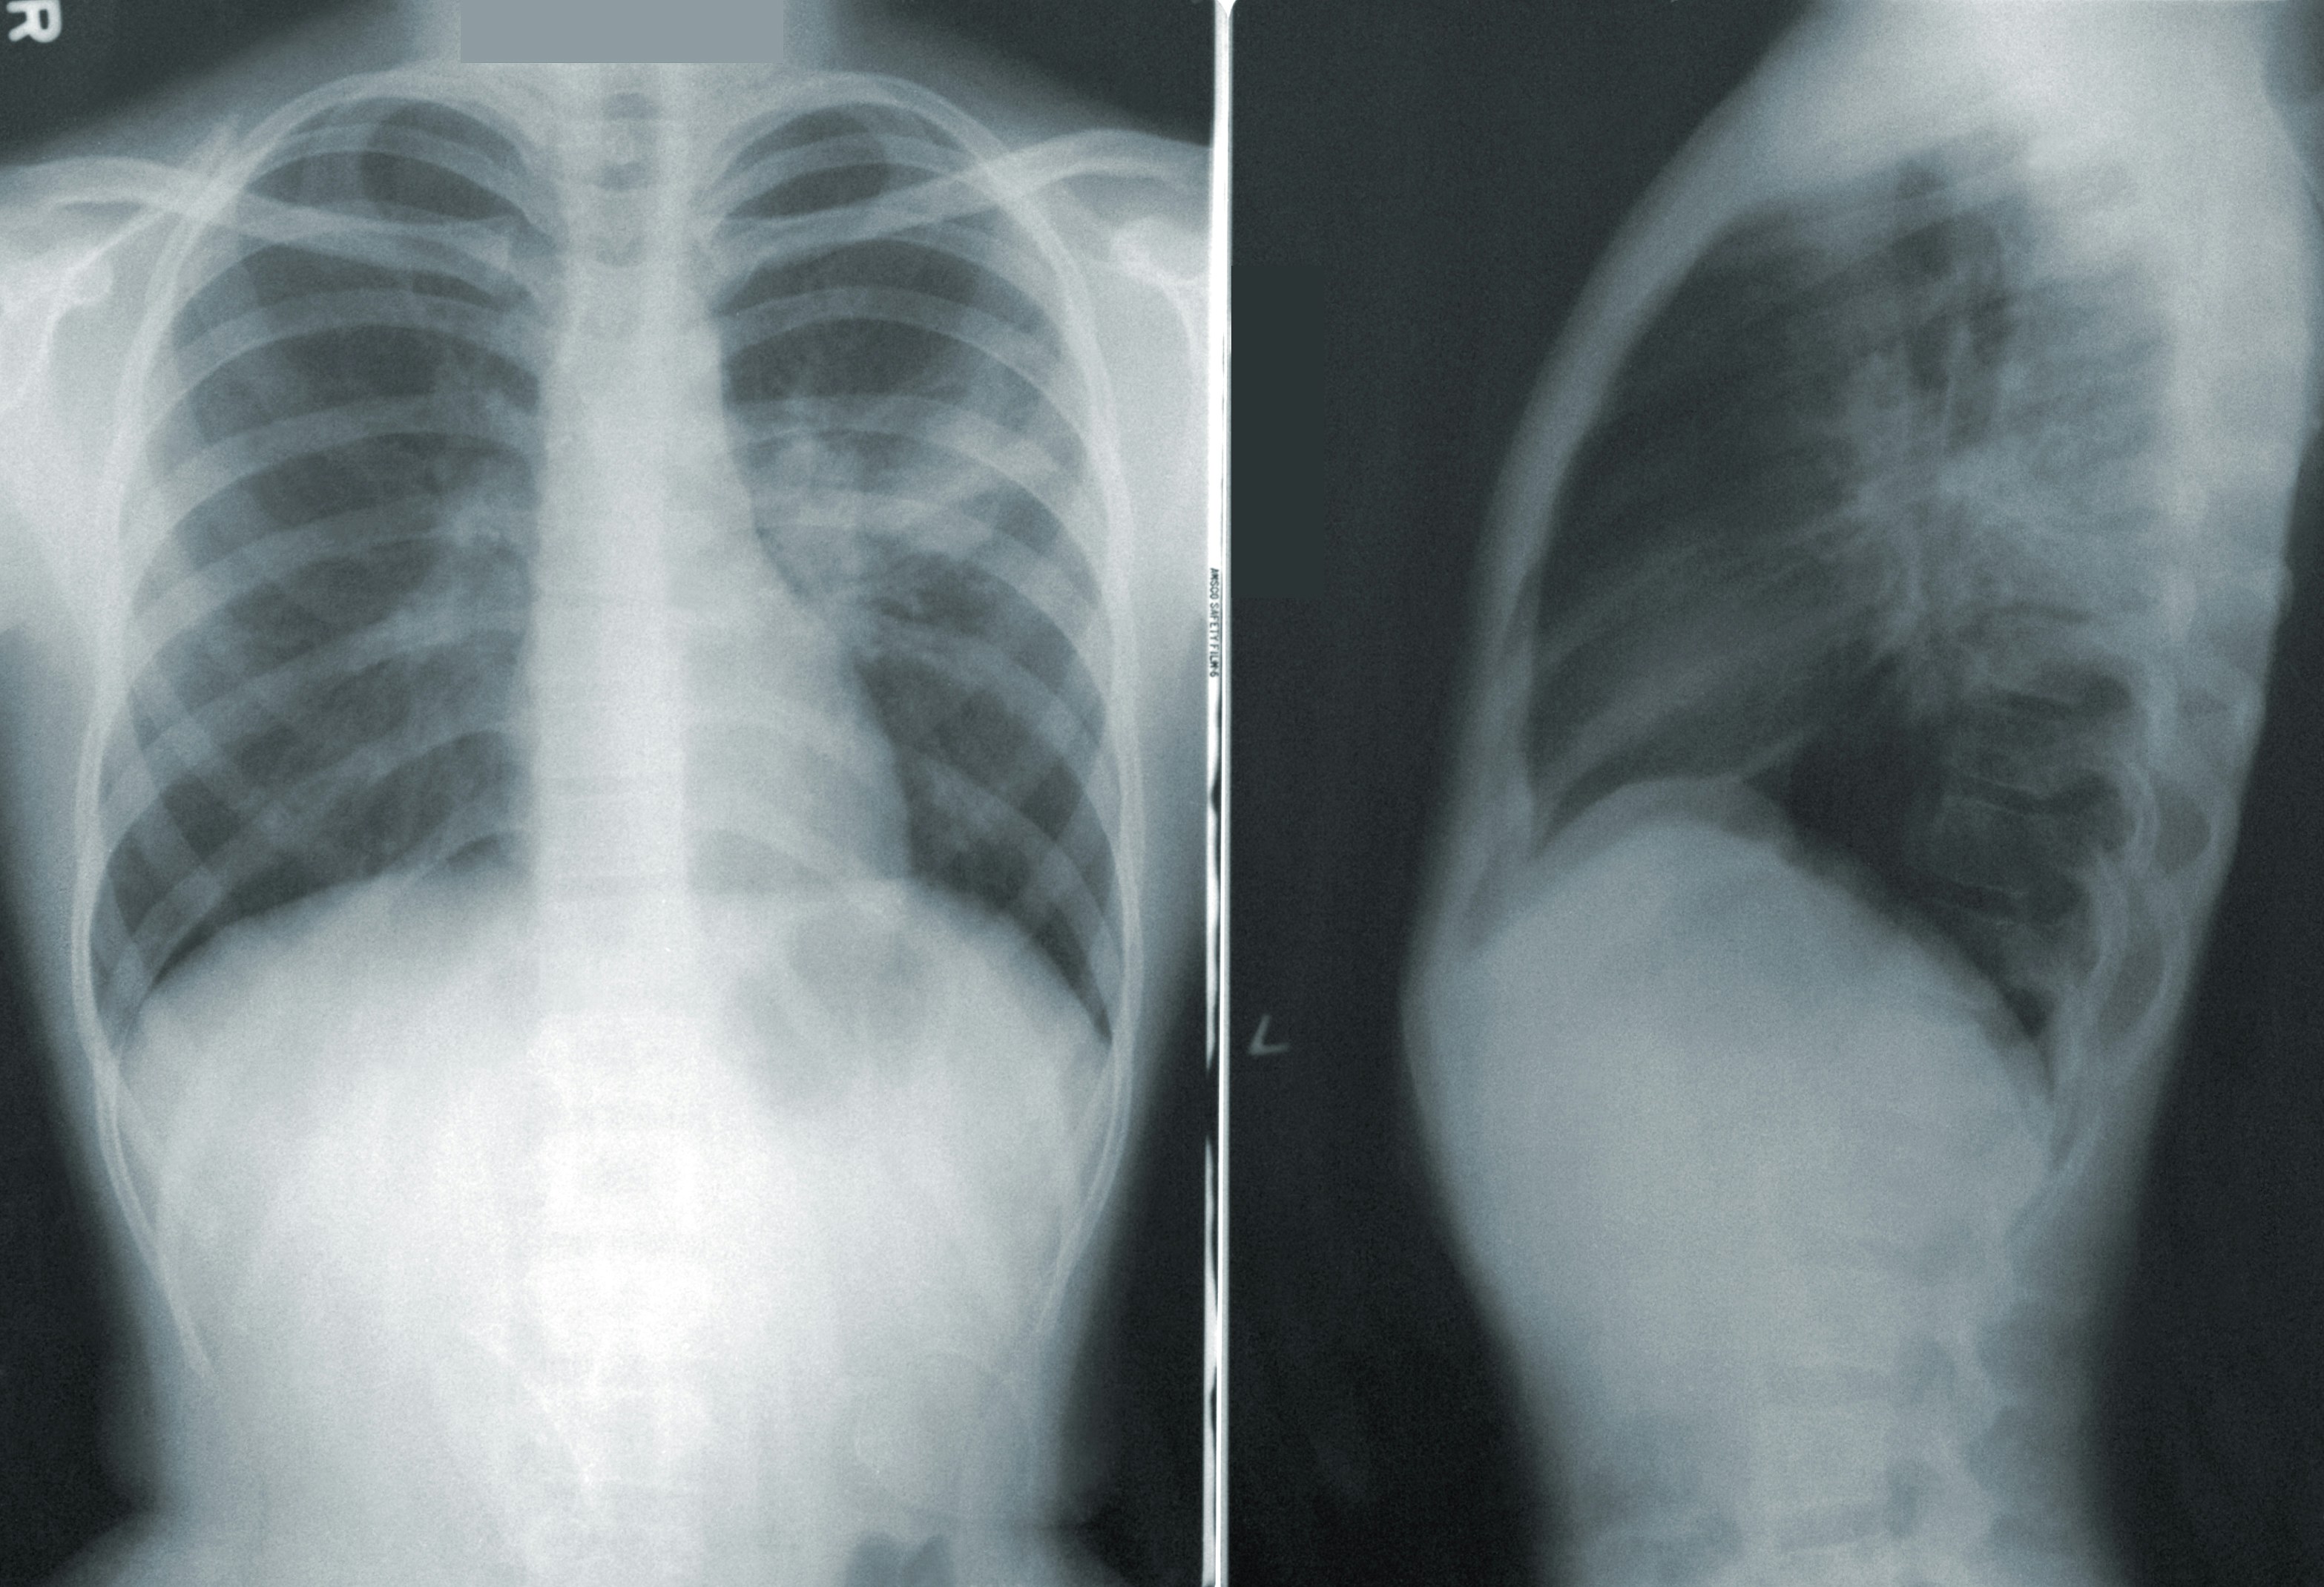

2. 소변검사 & 흉부 X-ray: 간단하지만 중요한 건강 신호

소변은 체내 노폐물을 배출하는 과정에서 나오는 결과물이기 때문에, 신장 기능과 여러 질환의 신호를 쉽게 파악할 수 있어요. 흉부 X-ray는 주로 폐와 심장 주변의 구조를 확인하는데 사용됩니다.

- 소변검사: 단백뇨가 나오면 신장에 이상이 있을 수 있어요. 혈뇨는 요로계 이상, 결석, 방광 문제를 의심해야 하고요.

당뇨가 심하면 소변에서 당이 검출되기도 해요. - 흉부 X-ray: 폐렴, 결핵, 폐암 등을 조기에 감별할 수 있어요. 특히 흡연자라면 꼭 챙겨야 할 검사입니다.

심장이 비대해졌거나 흉곽 내 구조물 변화도 함께 확인할 수 있어요.